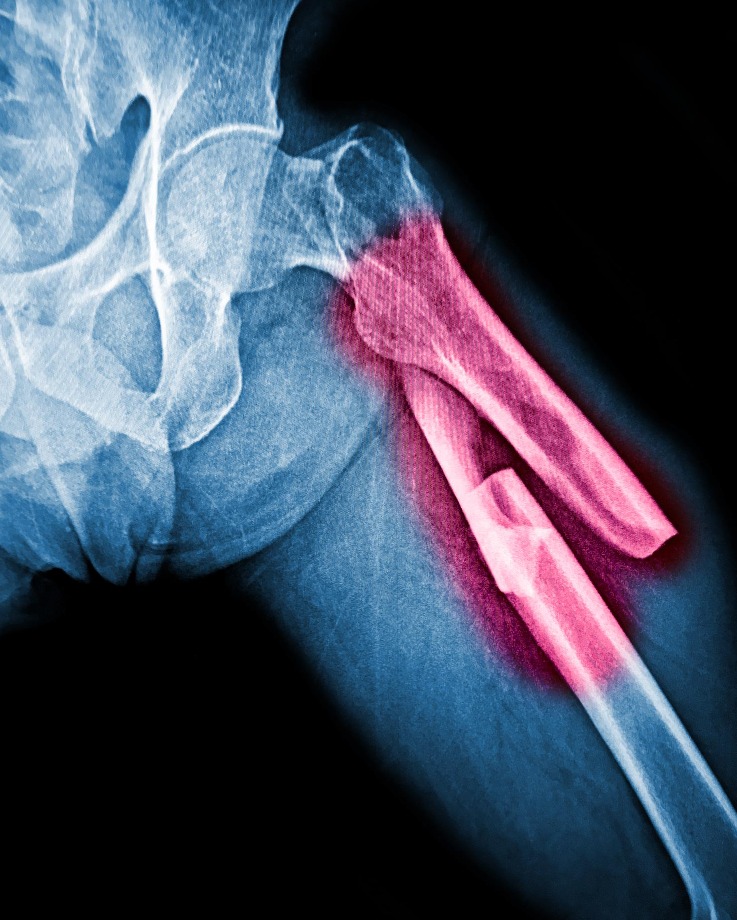

Best Fracture Specialist in Pune – Supporting Safe and Complete Bone Healing

Best fracture specialist in Pune is usually searched during moments of urgency. A fall, accident, or sudden injury can disrupt daily life instantly, making timely and accurate fracture care essential. Proper alignment and early treatment play a major role in how well the bone heals over time.

Fracture treatment today goes beyond simply placing a cast. It involves assessing the type of fracture, understanding joint involvement, managing pain, and planning rehabilitation to restore strength and mobility. Each fracture behaves differently, and treatment needs to be adapted accordingly rather than following a one-size-fits-all approach.